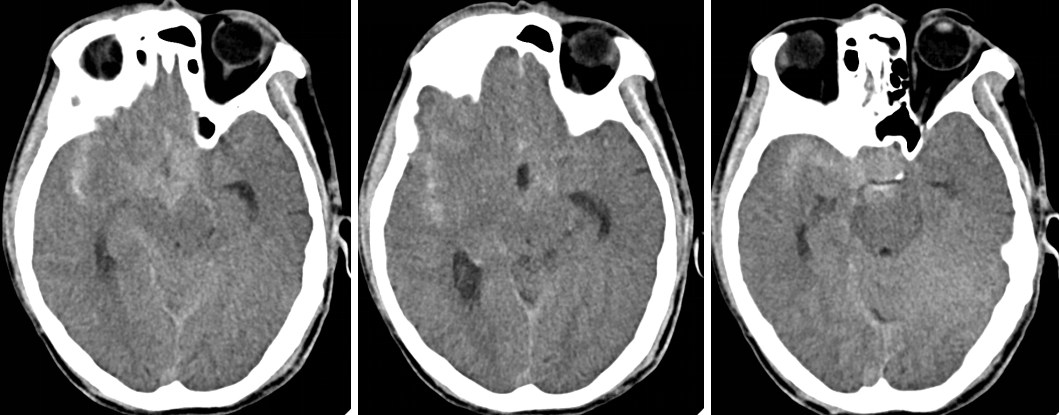

头颅CT

术后第1天CT

术后第1天CTA